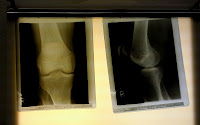

Heute morgen hat man im Krankenhaus festgestellt, dass wahrscheinlich nichts festzustellen war. Die Kernspin-Untersuchung hat ergeben, dass mein Knie wohl keinen "Macken" hat. Die Schmerzen stammen vermutlich von einer Überbeanspruchung der Wadenmuskeln.

Zyste in der Kniekehle

Eine Zyste in derKniekehle drückt auf einen Nerv und macht mir beim Laufen und Stehen große Probleme.

Da ich ein Mensch bin, der mit Ungewissheiten nur schlecht  leben kann, habe ich beschlossen, der Ursache sofort auf den Grund zu gehen und für nächste Woche einen Termin im Kernspind vereinbart. Wenn sich der Verdacht auf Meniskusriss bestätigen sollte, werde ich auch sofort das Messer ansetzten lassen.